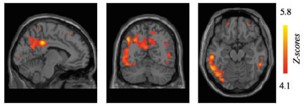

Identifying a biomarker of neuroinflammation for patient stratification in Alzheimer’s disease